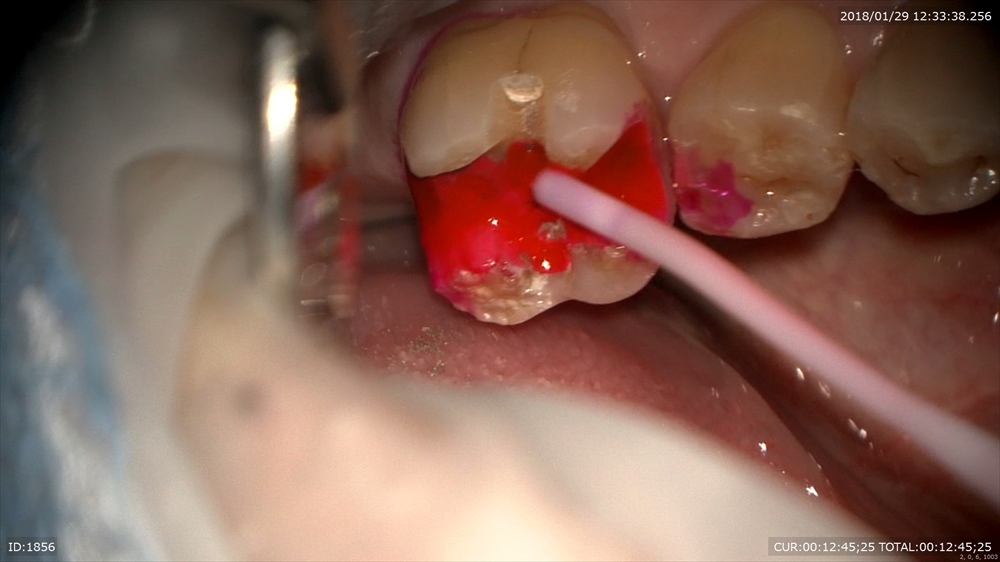

綺麗にして 検知液で確認!!

壁を作り型とりへ。